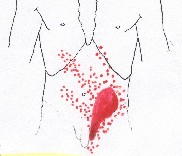

Pain referral

Trigger points

Internal Oblique Abdominis